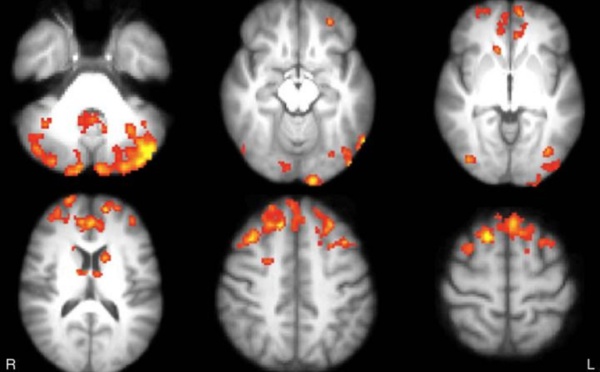

El 'Brain Training del Dr. Kawashima', un videojuego contra la esclerosis múltiple - 09/03/2016

La esclerosis múltiple es una enfermedad del sistema nervioso central que provoca daños cognitivos. Un equipo de investigadores ha descubierto ahora que estos daños pueden revertirse en parte en solo 8 semanas de entrenamiento mental con un videojuego de Nintendo.